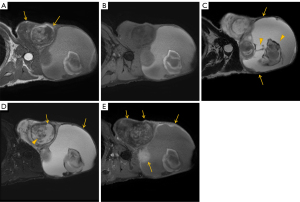

Representative MRI images are shown in Figures 1-3. Corresponding histopathological findings of the lesions in Figures 1,3 are shown in Figures 4,5, respectively.

In cases of fat-containing tumors, the T1WI signal intensity reflects fat content, which is diagnostically significant. Earlier studies have categorized ASPLT T1WI signal intensity into the following three groups: (I) high; (II) mixed high and low; and (III) low (6). However, since some high T1WI signals may be attributed to hemorrhage or myxoid components (8), this study focused on evaluating fat content using selective fat suppression techniques instead of T1WI signal intensity. Fat content varied widely, with an average score of 1.74 and median score of 1, indicating a tendency toward low fat content in the cases assessed. Histopathological examination similarly confirmed a tendency toward low fat content, with findings consistent with imaging in many cases (Figures 4A,5A). Furthermore, fat was not only interspersed within the nonfatty components but also often present as distinct nodules, which corresponded well with the MRI findings.

Regarding nonfatty components, T2WI high-signal areas appeared in 18 cases (94.7%), with 17 cases (89.5%) showing high-signal areas covering approximately 25% of the lesion. T2WI low-signal septa were observed in all cases. Contrast enhancement appeared in 15 of 16 cases (93.8%), predominantly in T2WI high-signal areas and in T2WI low-signal areas in 12 cases (75.0%). Histologically, abundant collagen fibers and myxoid material were observed in these lesions (Figures 4C-4E,5C-5E), which corresponded well with the signal characteristics on T2WI. Specifically, T2WI low-signal areas were considered to reflect collagen fibers, whereas high-signal areas were attributed to myxoid components. However, no discernible histological differences were observed that could account for the variation in contrast enhancement (i.e., moderate in Figure 4 and faint in Figure 5).

Other findings included well-defined margins in eight cases (42.1%) and capsular structures in 17 cases (89.5%). Margins have been reported to be indistinct owing to peripheral infiltration (2,4). In our pathological analysis as well, capsule-like structures were observed at the tumor margins; however, tumor infiltration beyond these structures was also identified in some areas (Figures 4B,5B). This suggests that the capsules observed on MRI may not represent true tumor capsules, but rather so-called “pseudocapsules” formed by compression or reactive changes in the surrounding tissue.